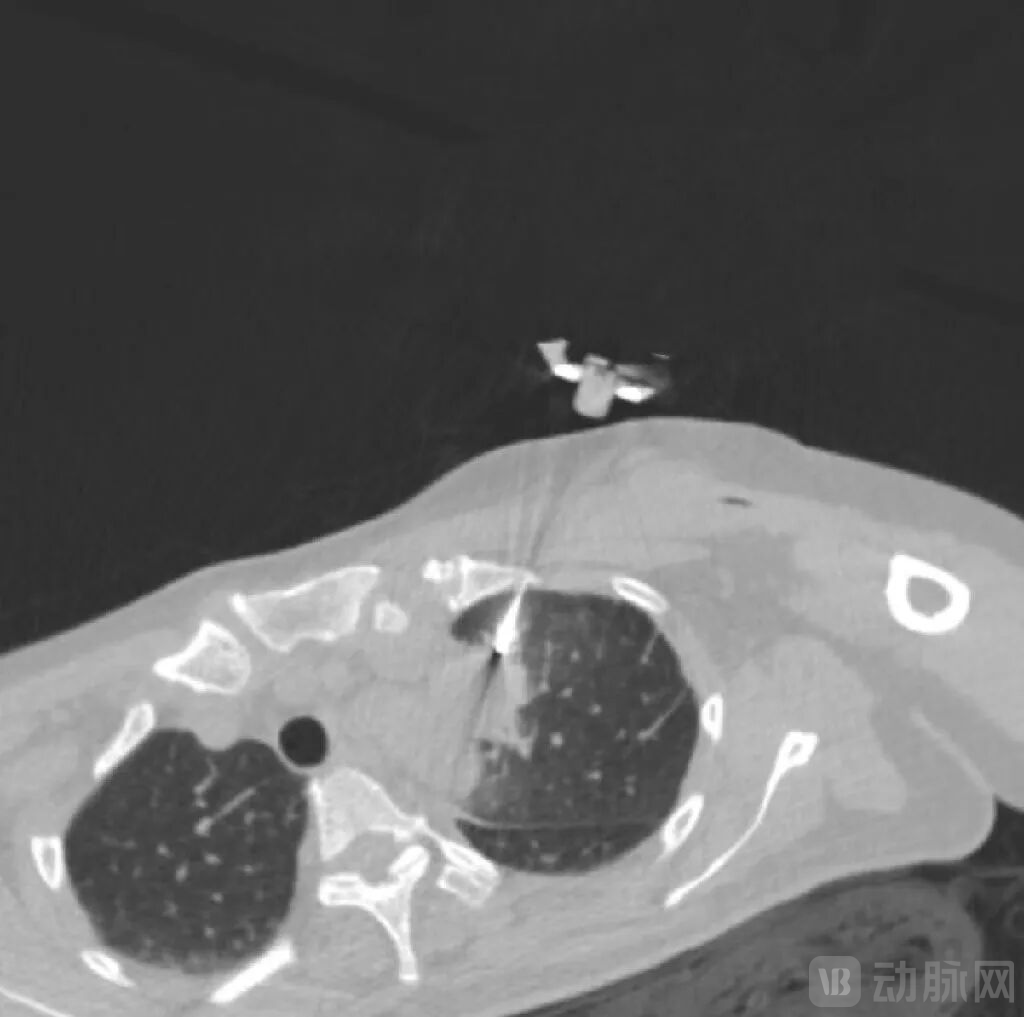

一例患者病例显示,在患者病灶粘连主动脉的情形下,MicrolGT-RoboC执行跨层穿刺规划,自动计算出进针位置及角度,精准穿到病灶。

RoboC规划执行图,图源:微引科技公众号